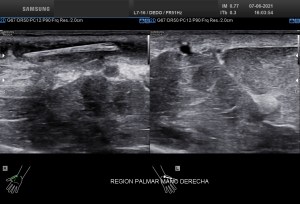

Recuerdo la importancia de comprobar siempre la permeabilidad de los vasos del hueco poplíteo con este tipo de patologías, el parecido de los síntomas de un quiste de Baker roto y la TVP puede ser muy similar y sin embargo, la TVP es una patología potencialmente peligrosa. Para ello pide al paciente que suba la pierna afectada por encima de su otra pierna para poder hacer que el retorno venoso sea más evidente y poder estudiar los mencionados vasos, sobre todo, su vena, claro.

La compresión con la sonda del hueco poplíteo establece la permeabilidad de la vena poplitea. Normalidad por tanto, manda, el comportamiento de la vena, compresible, y no el uso del doppler, por eso me permito el lujo de enseñarte la técnica sin el uso del doppler color. Línea roja: Si la vena no se colapsa.